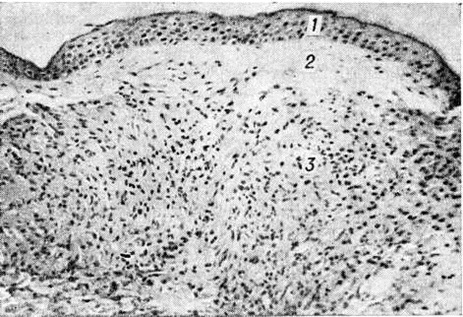

Рис. 8.

Микроскопическая картина кожной гранулемы при туберкулоидном типе лепры: поражение субэпидермальной зоны, инфильтрат состоит из эпителиоидных и лимфоидных клеток, 1 — эпидермис, 2 — субэпидермальная зона, 3 — инфильтрат. Окраска гематоксилин-эозином; × 120.

Рис. 1—6.

Микроскопические картины поражений при различных формах лепры.